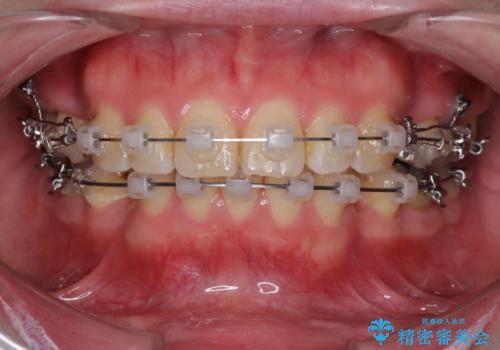

- クリアブラケット

- 2年2ヶ月

- 口が閉じずらく、口元が突出している状態でした。

上下左右の歯を1本ずつ、合計4本抜歯して、ワイヤーにて矯正することとなりました。

もともと下の前歯の永久歯が1本欠損しており、抜歯部位の選択を考慮しなければならない症例でした。シミュレーションを事前に行い、下顎の抜歯部位を決定しました。